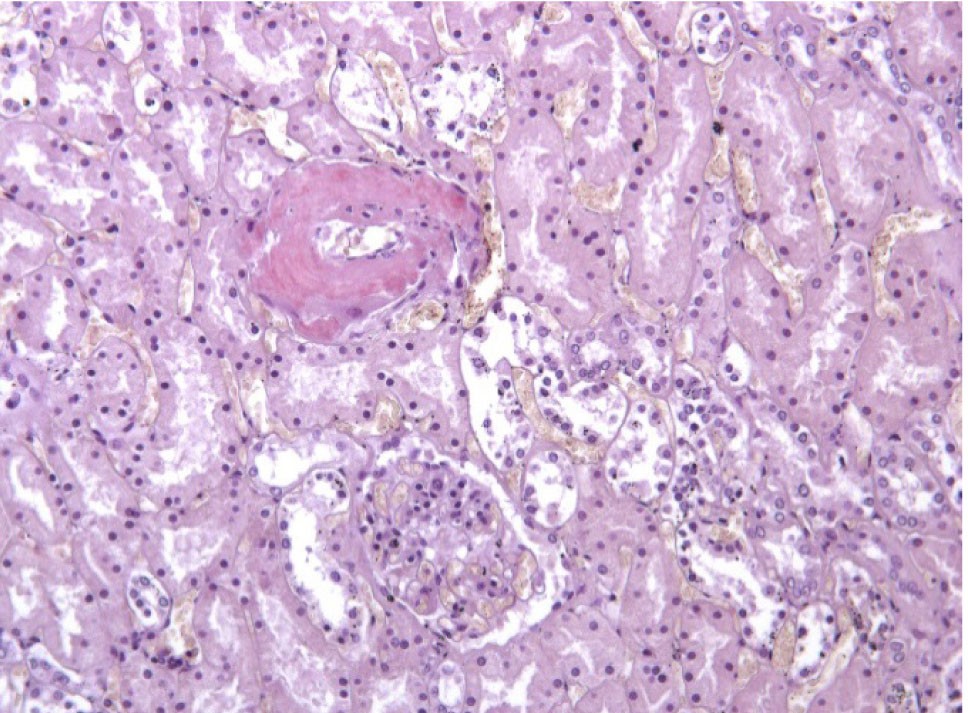

Рис. 1. Амилоид в строме и стенке сосудов сердца. Окраска гематоксилин-эозин, ×100

Гистологическое исследование. Сердце – кардиомиоциты гипертрофированы, диффузный кардиосклероз. При окраске на амилоид в строме и стенке сосудов отложение амилоидных масс (рис. 1). Селезенка – красная пульпа полностью замещена однородными массами, дающими положительную окраску на амилоид (рис. 2).